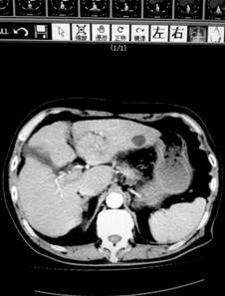

上午9點,第一肝門預(yù)阻斷后,肝臟手術(shù)正式開始,患者是一位80歲的肝癌患者,腫瘤位于肝左葉,合并肝炎并肝硬化,考慮患者肝功能較差,依據(jù)腫瘤根治原則,為患者成功實施了左肝外葉切除。目前該患者正在進一步康復(fù)。